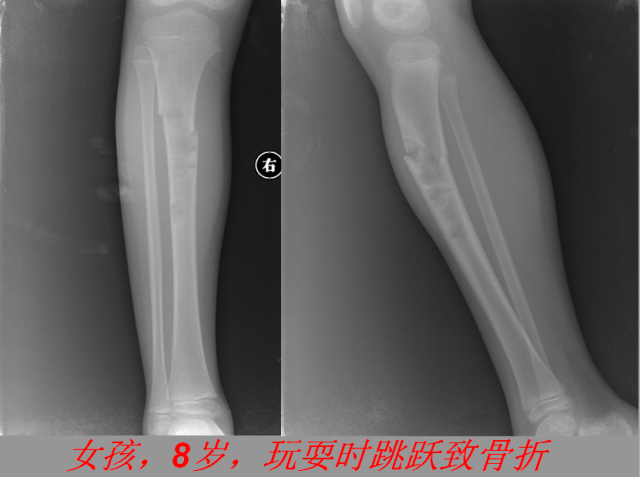

骨折篇

01

定义:骨折{Fracture}是指骨的完整性和连续性的折裂或粉碎。包括创伤性骨折、疲劳性骨折和病例理性骨折。 临床上以创伤性骨折*常见。